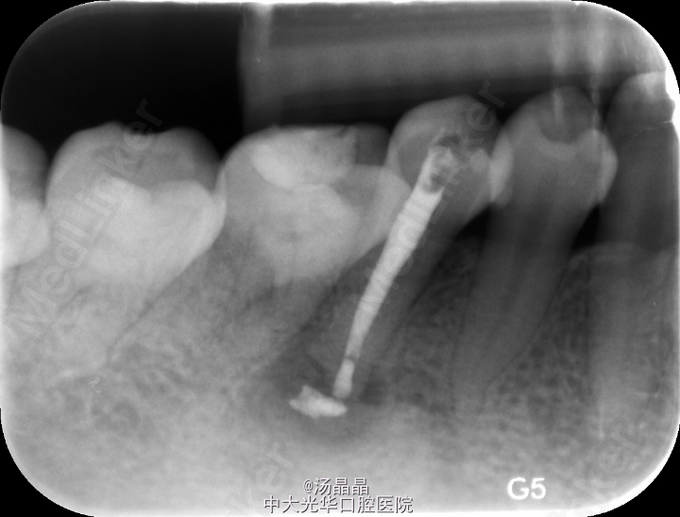

45咬合面探及深在龋损,叩(+—)松(-),X线:45根尖阴影,根尖孔闭合不全

45根尖周炎,去腐,探及一根管,疏通,预备后,封Vitapex,GIC暂封

3月复查,根尖阴影明显消失,换药,继续随访